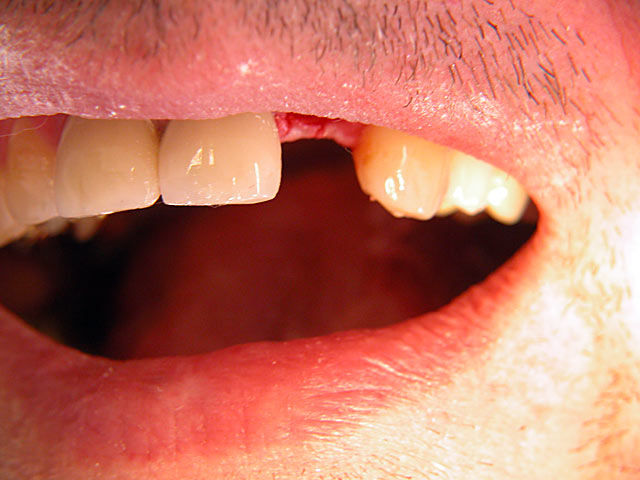

Frontzahn-Implantation: